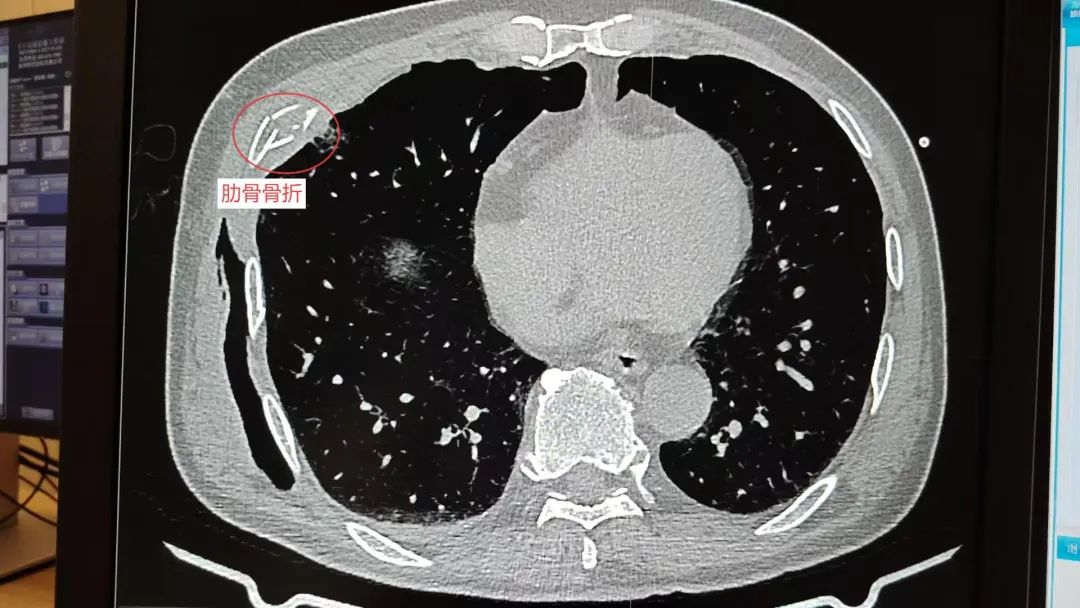

皮下气肿

系统检查提示:罗叔目前存在车祸后多发伤,头部、胸部、腹部等存在多处外伤,颅脑的挫裂伤,右侧颌面部撕裂伤,右肘关节皮肤裂伤等全身多处皮肤擦伤。外表的伤口已经足够狰狞,而在罗叔的身体内部存在更严重的情况:闭合性颅脑损伤、呼吸衰竭、右侧6根肋骨骨折伴血气胸和皮下气肿、代谢性酸中毒、呼吸性碱中毒,还有肝、肺挫伤等脏器损伤。